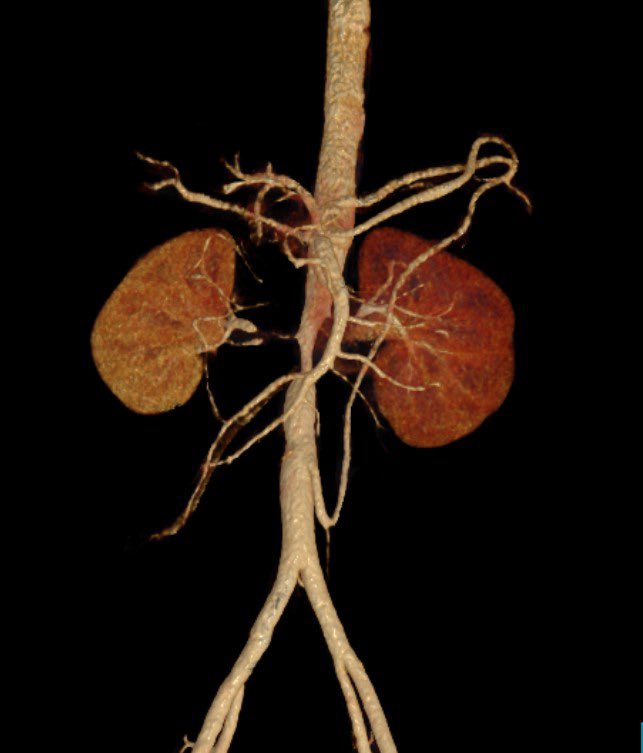

Another amazing #HIDI on #techniquetuesday from @SukguH @usc_vascular on in-situ laser fenestration! Some serious #aortaED right here, don't miss out! jvscit.org/article/S2468-… What other "how I do it" articles would @VascularSVS like to see published?